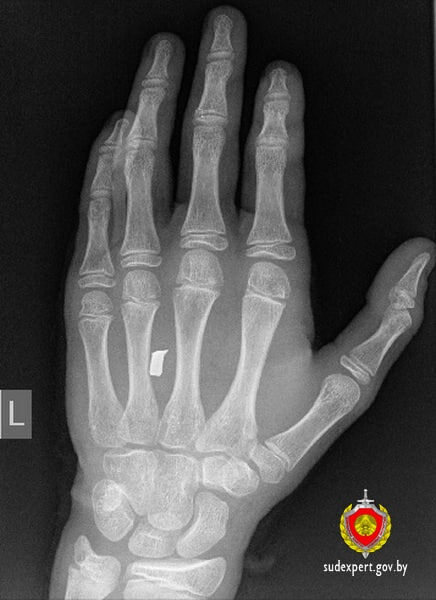

❗️В Петриковском районе 13-летний подросток прострелил руку строительным патроном

❗️В Петриковском районе 13-летний подросток

прострелил

руку строительным патроном